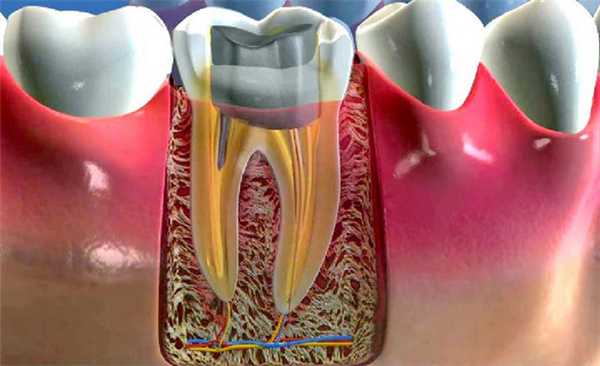

Вкладка является цельнолитым изделием, внешне напоминающим миниатюрный зуб. Микропротез состоит из верхней части (культи, обточенной под коронку) и «ножек» в виде штифта, которые интегрируются в корневой канал. На культю (отсюда и название вкладки) с помощью специального цемента крепят искусственную коронку.

Почему культевая вкладка лучше зубного штифта

На следующем этапе вкладку устанавливают. Главные требования к материалу для вкладок: твердость, инертность, упругость, а также низкие коэффициенты теплопроводности и усадки. В качестве закрепляющего состава для конструкции используется композитный цемент. Минипротез перед установкой обезжиривают. Зуб обрабатывается антисептиком и просушивается. Каналы заполняют цементом. При протезировании многоканального зуба цемент наносят на основной штырь, а после установки конструкции, закрепляющим составом покрывают и дополнительные штыри. После затвердевания конструкции, ранее подпиленные вспомогательные «ножки» отламывают, а следы излома полируют. При следующем посещении специалист проводит подготовку к установке искусственной коронки на зуб.